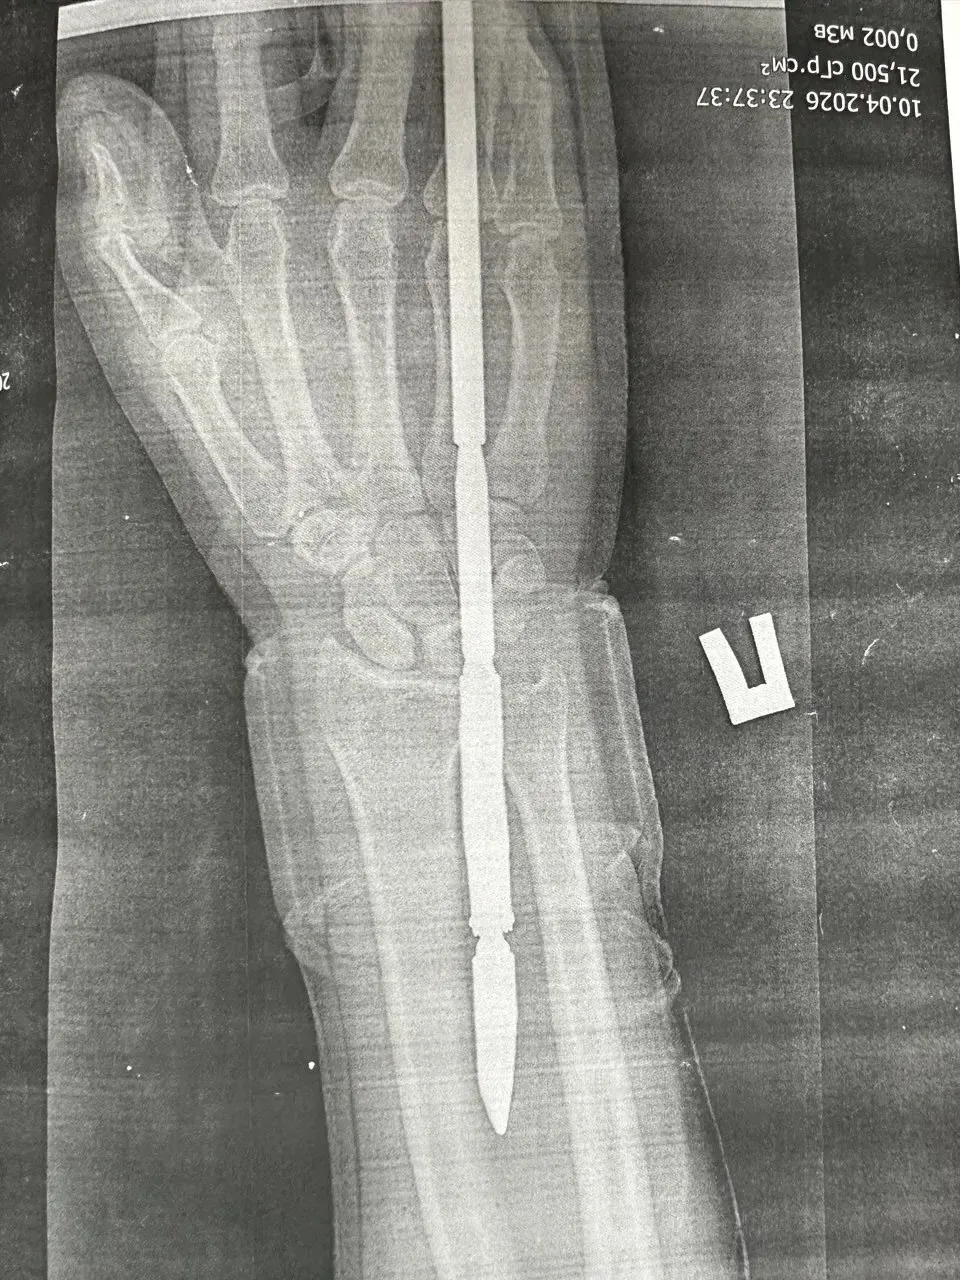

В отделение травматологии и ортопедии ГБ Орска поступил 29-летний мужчина, который загарпунил себя во время подводной охоты в Гайском округе. Гарпун с двумя зубцами прошёл между костями, не задев их.

Врачи извлекли инородное тело, обработали рану и оказали помощь. Сейчас пациент в хирургическом стационаре.